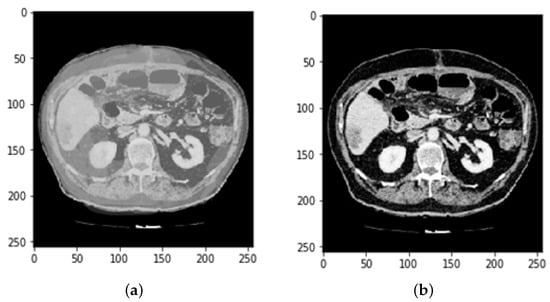

3.2. CT and MRI Images Preprocessing